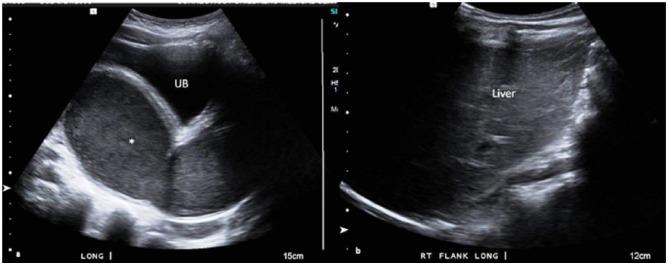

A Variant of Herlyn-Werner-Wunderlich Syndrome Presenting With Acute Abdomen: A Case Report and Review of Literature.

https://cdn.ncbi.nlm.nih.gov/pmc/blobs/e155/5946351/7e603d16b7ef/10.1177_2333794X18769817-fig1.jpg